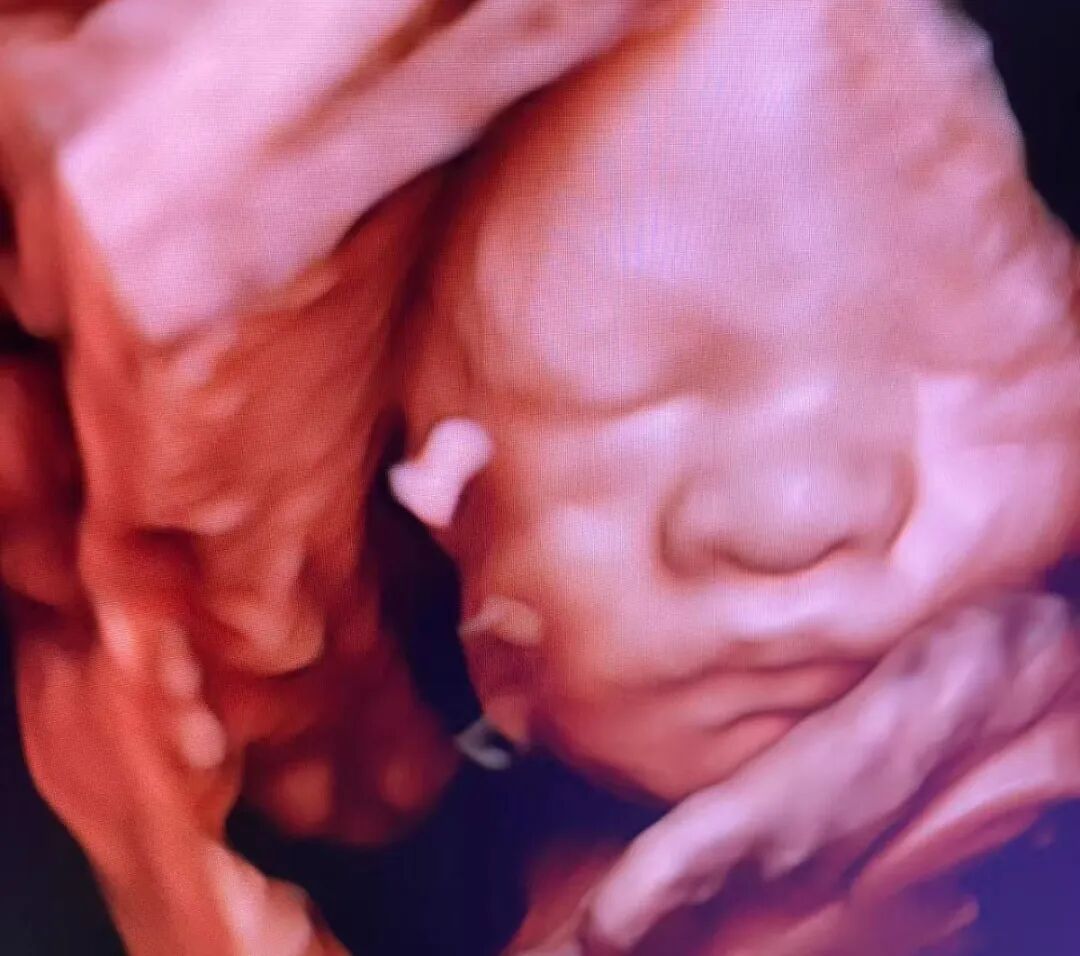

做四维彩超,本是孕期最令人期待的时刻之一——终于可以清晰地看到宝宝的小模样了!小家伙却常“闹小脾气”:睡觉、捂脸、背对镜头...就是不摆“完美pose”。

海南菁华生殖妇产医院B超室的医师们天天和“小调皮”打交道,今天就来给大家支支招,让您和宝宝的第一次“清晰会面”更顺利!